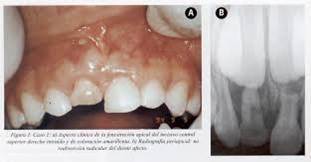

1. Anomalías en los Dientes

1. Dientes en Estaca, Dientes dilacerados, Dientes Primarios o Caducos, Hipopituarismo.